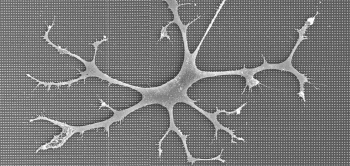

Microglia zijn de immuuncellen van het brein.

Microglia zijn immuuncellen die de hersenen vrij houden van ziekteverwekkers door ze ‘op te eten’ en te verteren.